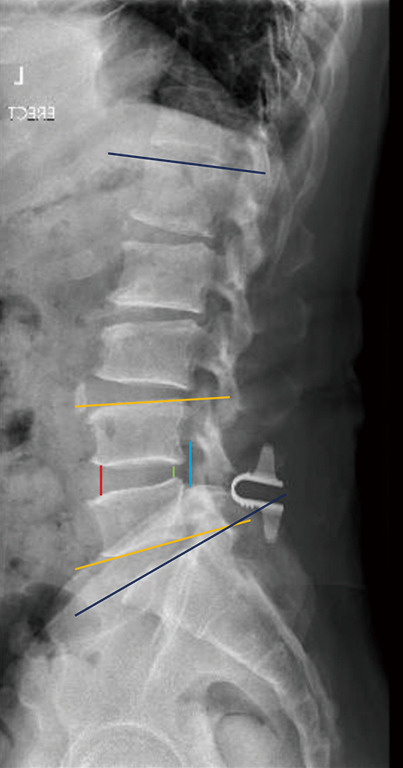

背景:与单纯减压术(DA)相比,使用层间器械作为减压术的辅助手段来治疗症状性腰椎管狭窄症(LSS)的放射学结果方面的文献十分有限。本研究旨在评估和比较脊柱减压术和带 ILD 的减压术(D+ILD)的 5 年放射学疗效:我们对前瞻性收集的数据进行了回顾性分析,这些数据来自 2007-2015 年间接受脊柱减压术并植入或未植入 ILD 的 94 例患者。符合研究标准的无症状 LSS 患者可接受脊柱减压术,无论是否植入 ILD。接受ILD植入的患者被归入D+ILD组(39人);而选择DA的患者被归入DA组(55人)。对术前、术后即刻、术后 2 年和 5 年的放射学指标进行评估:结果:共有 94 名患者,DA 组 55 人,D+ILD 组 39 人。两组患者的矢状平衡参数,即平均骨盆入径、骨盆倾斜、骶骨斜度和骨盆入径减去腰椎前凸(PI - LL)在术后 5 年的随访中均无明显变化。两组间的矢状平衡参数无显著差异。DA组与D+ILD组相比,整体前凸无明显差异,但D+ILD组的矢状角(指数水平)比DA组明显减少了2.3°(P=0.01)。在对照组中,术后椎间盘前部、椎间盘后部和椎间孔高度无明显差异。与对照组相比,D+ILD组的前椎间盘高度、后椎间盘高度和椎间孔高度平均分别增加了1.3毫米、1.8毫米和4.7毫米。两组患者的所有临床结果均有明显改善,即 36 项简表调查身体部分摘要(SF36 PCS)、36 项简表调查精神部分摘要(SF36 MCS)和视觉模拟量表(VAS)。比较两组患者,D+ILD 组的 SF36 MCS 有明显改善(P=0.01),但 SF36 PCS 和 VAS 没有差异。再手术率相当:我们的研究发现,在腰椎管狭窄症的治疗中,使用ILD作为辅助设备与DA相比,可显著改善椎间盘前部、椎间盘后部和椎管峡部的高度,预计干预水平的局灶性椎体后凸在5年后不会改变腰椎前凸和矢状平衡。

Results: There were a total of 94 patients with 55 in the DA group and 39 in the D + ILD group. In both groups, there was no significant change post-operatively in the sagittal balance parameters namely, the mean pelvic incidence, pelvic tilt, sacral slope and pelvic incidence minus lumbar lordosis (PI - LL) during the 5-year follow-up. Comparing between the groups, there was no significant difference in sagittal balance parameters. Comparing between DA versus D + ILD, there was no significant difference in overall lordosis, but the D + ILD had a significant reduction in sagittal angle (at the index level) of 2.3° compared to the DA group (P=0.01). In the control group, there was no significant difference in the anterior disc, posterior disc and foraminal height post-operatively. In the D + ILD group, there was a significant mean increase of 1.3 mm in anterior disc height, 1.8 mm in posterior disc height and 4.7 mm in foraminal height compared to the control group. In both groups, there was significant improvement in all clinical outcomes namely 36-item short form survey physical component summary (SF36 PCS), 36-item short form survey mental component summary (SF36 MCS) and visual analogue scale (VAS). Comparing the groups, there was significant improvement in the D + ILD group in SF36 MCS (P=0.01) but no difference in SF36 PCS or VAS. Reoperation rates were equivalent.